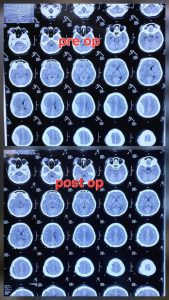

७० वर्षीया वृद्धालाई गम्भीर टाउको चोट लागेर होस गुमेको र बान्ता गरिरहेको अवस्थामा यस हस्पिटलको आकस्मिक कक्ष (ER) मा ल्याइयो। तत्काल CT स्क्यान गर्दा मस्तिष्कभित्र रगत देखियो। धेरैपटक सम्झाइबुझाइ गरेपछि मात्र परिवारले शल्यक्रिया गर्न स्वीकृति दिए। आज उहाँ बाँच्नुभएको छ र डिस्चार्जको तयारीमा हुनुहुन्छ।